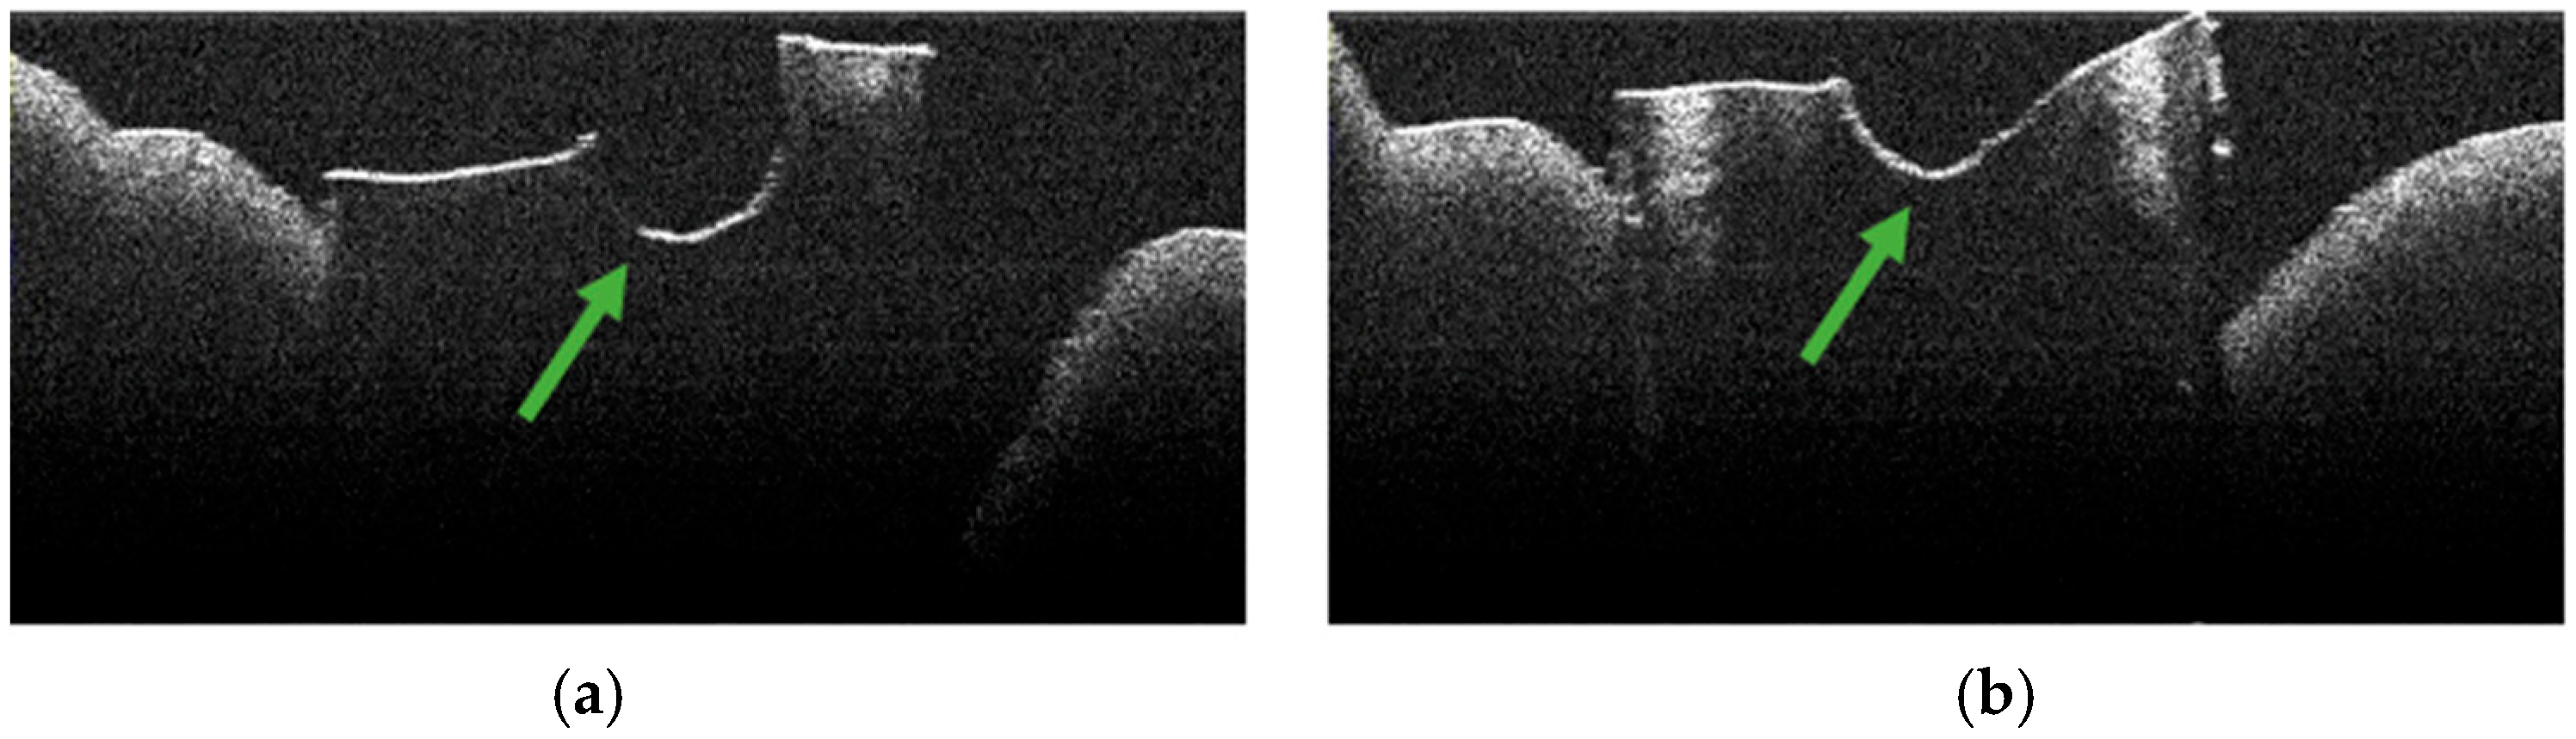

3.4. OCT Examination of Specimens from Group A

3.6. Topographic Distribution

3.7. Frequency of TIMAs